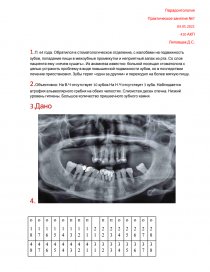

2.Объективно: На В.Ч отсутствует 10 зубов.На Н.Ч отсутствует 3 зуба. Наблюдается атрофия альвеолярного гребня на обеих челюстях. Слизистая десен отечна. Низкий уровень гигиены. Большое количество пришеечного зубного камня.

4. [pic 1]

2. Исходя из ОПГ мы можем сделать несколько выводов.

1.У пациенты все признаки парадонтита в хронической стадии (парадонтоза)

2.Отсутствует 13 зубов.

3. Ранее проводилось терапевтическое лечение при котором:

Было проведено эндодонтическое лечение 1,2 1,3 2,2 2,3 зубов